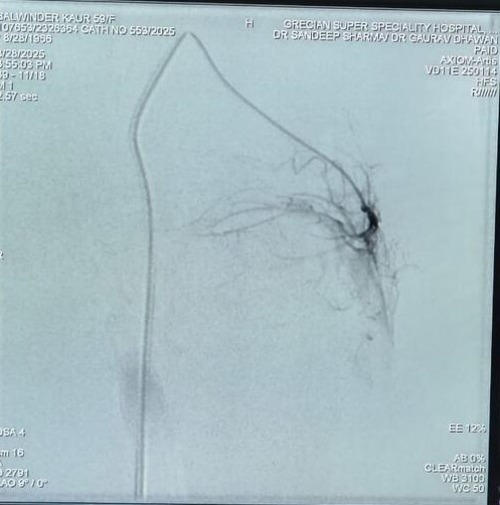

Balwinder Kaur Journey to Knee Pain Relief: A Successful GAE Treatment Story

Genicular Artery Embolization